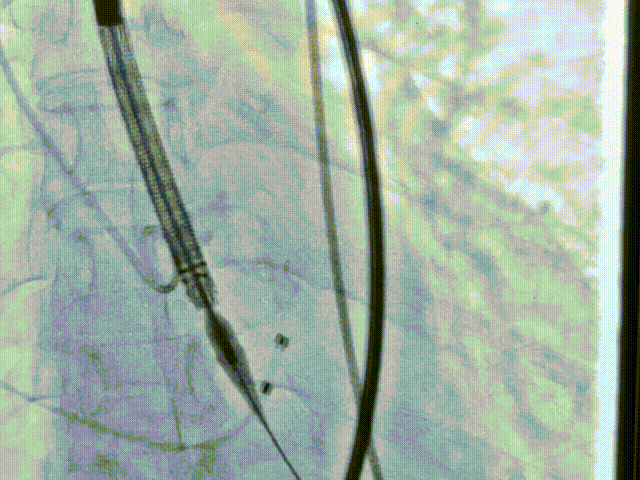

起始释放

第一次释放

位置稍深,选择回收,重新定位释放